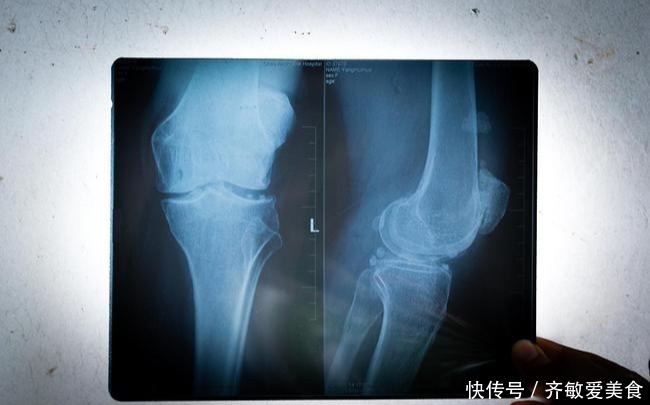

一位陈阿姨,今年60岁了,刚刚在教师的岗位上退休下来,儿子也是刚刚结婚,没什么可牵挂的,于是就拿着退休金约着小姐妹们出去玩,日子倒也是过得很充实,但是在前一段去检查身体的时候,却发现陈阿姨的骨密度已经处于-2.6了,已经是骨质疏松的范畴了。

在医生的解释下,陈阿姨意识到是之前出去玩的时候不良的饮食习惯导致的,于是就遵从医嘱,改掉了之前不良的饮食习惯,而且也开始培养日常良好的生活习惯,经过两个月之后去医院复查的时候,骨质已经稳定住了,并且还有一定程度的上涨,说明陈阿姨的办法对于骨质疏松起作用了。 陈阿姨平时经常吃这3种食物,损害了自身的骨骼健康,我们也要注意